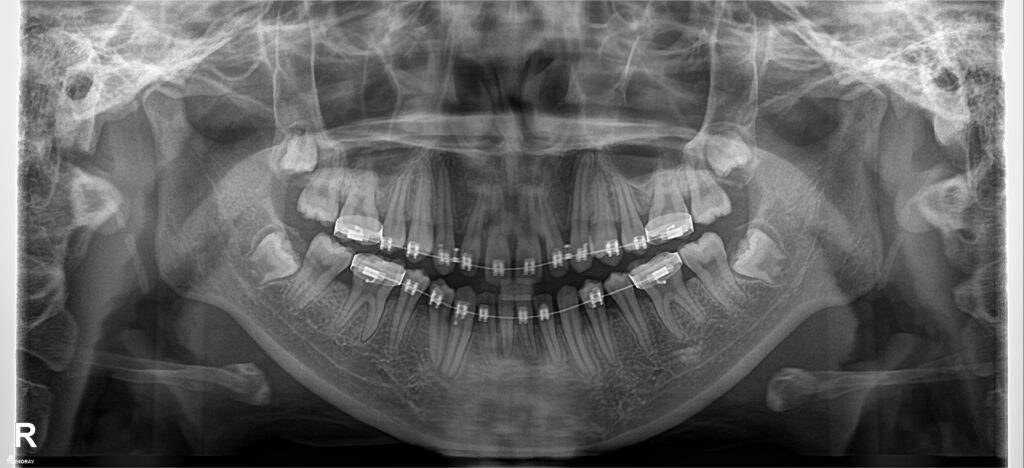

Bệnh nhân nữ sinh năm 2004 đã được điều trị tại 1 cơ sở nha khoa khác hơn 1 năm nhưng không cải thiện được tình trạng răng thưa, tình trạng việm lợi & hôi miệng cũng làm người nha BN lo lắng, không yên tâm trong công tác điều trị, cuối cùng có những khúc mắc ngoài lề giữa bác sĩ và người nhà nên BN không tiếp tục điều trị ở cơ sở cũ mà chuyển cơ sở điều trị khác.

Đánh giá: một trường hợp khe thưa răng cửa giữa hàm trên rất hay gặp trên lâm sàng, nếu không đánh giá đúng tính hình có thể rất dễ bị tái phát do vấn đề khớp cắn, khi đong khe thưa không căn chuẩn thì đường giữa hai răng cửa hàm trên sẽ lệch so với đường giữa mặt (lệch đường giữa hàm trên) và đường giữa hàm dưới có thể không thẳng đường giữa hàm trên.

Phương án: đóng khe thư nhóm răng cửa trước, đánh giá cẩn thận khi đóng khe thưa răng cửa giữa hàm trên và hàm dưới kĩ lưỡng, đưa đường giữa về vị trí chuẩn, sau đó mới đóng hết khoảng và tinh chỉnh khớp cắn.

Kết quả: đường giữa đẹp, khớp cắn ổn sau 1 năm điều trị. Tuy nhiên, BN đeo niền lâu & yếu tố tuổi dạy thì làm tình trạng việm lợi- phì đại lợi tồn tại. BN được tháo mắc cài, hướng dẫn CSRM kĩ lưỡng kèm mát xa lợi, đeo hàm duy trì máng trong. Kết qảu tái khám rất ổn sau 6 tháng.